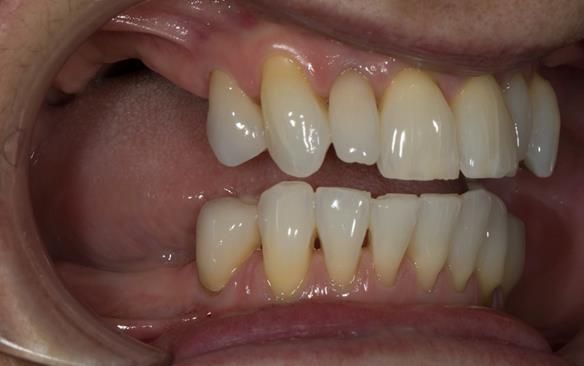

This newsletter describes in step by step detail Angela's transition through immediate partial dentures to crown supported definitive metal based dentures.

This 58 year old woman was referred to me by her general dental practitoner for treatment.

- Generalised Periodontitis; Stage 4, Grade C, Currently Unstable. Risk Factors: Type 1 diabetes. 16, 17 - hopeless prognosis. 14, 24, 26, 27, 34, 37, 44 - guarded prognosis

- Poor marginal fit and poor appearance of crowns and bridgework

- Yellowing teeth

The clinical situation and treatment process is shown in detail below with photographs. I (Finlay Sutton) provided the clinical work and Rowan Garstang provided the technical work.